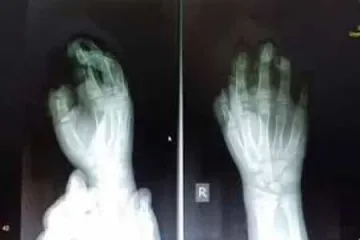

Ռուստամ Բադասյանը ներկայացրել է Նարեկ Մալյանի դեմ քաղաքացիական հայցի բովանդակությունը ԱԱԾ-ն քննադատությունների կիզակետում է Ի՞նչ է նվիրել Էրդողանը Պուտինին Ինչպես իրանցիները, այնպես էլ ամերիկացները բլեֆ են անում. ռուսաստանցի փորձագետ Ալումյան. «Հիմա ես աշխատում եմ Քոչարյանի գործով Եվրադատարան ներկայացվելիք գանգատի վրա» Պայթուցիկից տուժած երեխայի երկու մատը վերականգնվել է ՀՀ անձնագրով առանց վիզայի կարելի է այցելել 62 երկիր. հրապարակվել է 2020-ի ինդեքսը Հրապատիճը պայթել է 9-ամյա աղջնակի ձեռքի մեջ եւ հարվածել դեմքին. երեխան հիվանդանոցում է Թավադյանից ֆինանսական միջոցներ են առգրավել առանց տրամաբանության. (տեսանյութ) Պուտինը եւ Էրդողանը բացել են «Թուրքական հոսքը» Անաստասիա Վոլոչկովային լուսանկարել են սիրելի հետ, որին նա երկար ժամանակ թաքցնում էր Ռոման Բերեզովսկին՝ «Փյունիկ»-ի գլխավոր մարզիչ Սա ճնշում է հեռուստաընկերության վրա․ Հարություն Հարությունյանը՝ Թավադյանի կալանքի մասին Իրաքի իշխանությունները նախազգուշացրել էին ԱՄՆ-ին, թե Իրանը որ բազաներին է հարվածելու Դատախազությունը մերժել է Արմեն Թավադյանի նկատմամբ ընտրված խափանման միջոցը փոխարինելու վերաբերյալ միջնորդությունը Armenia Airways-ը կշարունակի Երևան-Թեհրան-Երևան ուղղությամբ չվերթները Գարեգին Բ-ն անդրադարձել է 2020-ի ծրագրերին եւ նախաձեռնություններին Ուզբեկստանում Գուլնարա Քարիմովայի գործով նոր դատավարություն է սկսվել Թուրքիայի ԱԳ նախարարը վերջին դեպքերի հետ կապված հունվարի 9–ին մեկնում է Իրաք Ուկրաինան դադարեցնում է ուկրաինական ավիաընկերությունների թռիչքները Իրանի օդային տարածքում «Մենք ծնելիության կտրուկ անկման խնդիր ունենք». Գեւորգ Պետրոսյանը՝ Մարալիկի ծննդատունը փակելու մասին Դռան փականից կախված 10-ամյա տղան գիտակցության է եկել ու սկսել է շնչել ինքնուրյուն Դոլարի փոխարժեքը էլ ավելի մոտեցավ 480 դրամի սահմանագծին. Եվրոն էժանացել է ավելի քան 3 դրամով Հովհաննես Ազոյանը տուժող է ճանաչվել Հրազդանի կիրճում տեղի ունեցած միջադեպի գործով «Ուկրաինայի միջազգային ավիաուղիների» նախագահը չի կարողացել զսպել արցունքները Ավստրալիայի հրդեհների ծուխը հասել է մինչև Չիլի և Արգենտինա (տեսանյութ) 16-ամյա աղջկան խեղդելու կասկածանքով ձերբակալվածին մեղադրանք է առաջադրվել «Տեսլա» ընկերության բաժնետոմսերի գինը վերջին երեք ամսվա ընթացքում կրկնապատկվել է 2020 թվականին Հայաստանում գները կաճեն 0,5 տոկոսի սահմաններում. փորձագետ Իրանական օդանավակայանից հայտնել են ուկրաինական ինքնաթիռի կործանման պատճառը (տեսանյութ) Ամերիկյան ցանկացած նոր չարիք ավելի կոշտ եւ վճռորոշ պատասխան կստանա. Իրանի ԶՈւ ԳՇ պետ Իրանում կործանված ուկրաինական ինքնաթիռի անկման վայրում գրություն են գտել (լուսանկար) ՀՀ-ում Իրանի դեսպանատանը սգո մատյան կբացվի Ղասեմ Սոլեյմանիի մահվան կապակցությամբ Եվրահանձնաժողովի ղեկավարն ԱՄՆ-ին եւ Իրանին կոչ է արել անհապաղ դադարեցնել զենքի կիրառումը Երկու ուղեւոր չի նստել Թեհրանում կործանված ինքնաթիռ ԱԺ-ի կեղծ մեդալների ձեռքբերման գործընթացում չարաշահումների համար 2 անձի մեղադրանք է առաջադրվել «Վիրաբուժականը փակեցին, ինֆեկցիոնը փակեցին, հիմա հերթը ծննդատանն է. Էդ նախարար չէ, մոլախոտ է». Մարալիկի բնակիչներ ՈւԵՖԱ նախագահը՝ ՀՖՖ նախագահին․ Մաղթում եմ լուրջ հաջողություններ այս պաշտոնում Ստամբուլում մեկնարկել է Պուտինի եւ Էրդողանի հանդիպումը Ինչպե՞ս վերադառնալ նորմալ սննդակարգի ամանորյա տոներից հետո Եղանակը Հայաստանում. առանձին շրջաններում եւ Երեւանում սպասվում են տեղումներ ԿԳՄՍ նախարարության մասին դրական հոդվածներ չեն դիտարկվել. «Մեդիա Պաշտպան» Պատասխան հարված կհասցնենք ցանկացածի ուղղությամբ, ով կհարձակվի Իսրայելի վրա. Նեթանյահու Նիկոլ Փաշինյանը ցավակցել է Թեհրանում օդանավի աղետից զոհվածների հարազատներին ՍԴ նախագահ Հրայր Թովմասյանի սանիկին կալանավորելու վերաբերյալ որոշումը կհրապարակվի վաղը Ղասեմ Սոլեյմանին ճկուն դիրքորոշում ուներ ղարաբաղյան խնդրում. իրանագետ Դասախոսներին ու ուսուցիչներին պահում են սովի մեջ, իսկ իրենք պարգևատրվում են. Գևորգ Պետրոսյան Պոպուլիզմն ազգություն չունի Վայոց Ձորում ծեծի ենթարկված փոխգնդապետ Արա Մխիթարյանի առողջական վիճակը չի փոխվել, նա դեռ կոմայի մեջ է Բրիտանիայի ԱԳ նախարարը դատապարտել է Իրաքում ԱՄՆ բազաներին Իրանի հարվածները